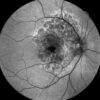

✓ Autofluorescence mode